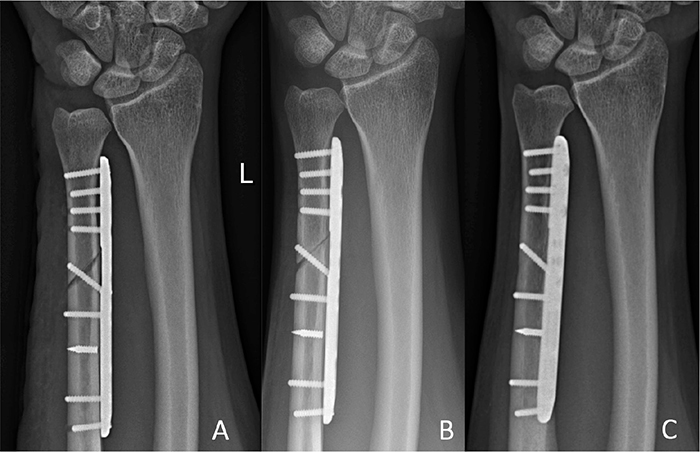

Figure 5. Posttraumatic loosening case. Radiographs (A) 2 months postoperatively with plate loosening after fall on the ipsilateral hand; (B) 12 months after the revision-osteosynthesis; and (C) at last follow-up 36 months postoperatively.